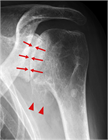

1. 肩関節の痛みの原因として、腱板断裂、石灰性腱炎、凍結肩(五十肩、肩関節周囲炎)、変形性関節症を想起すべきである(推奨度1)